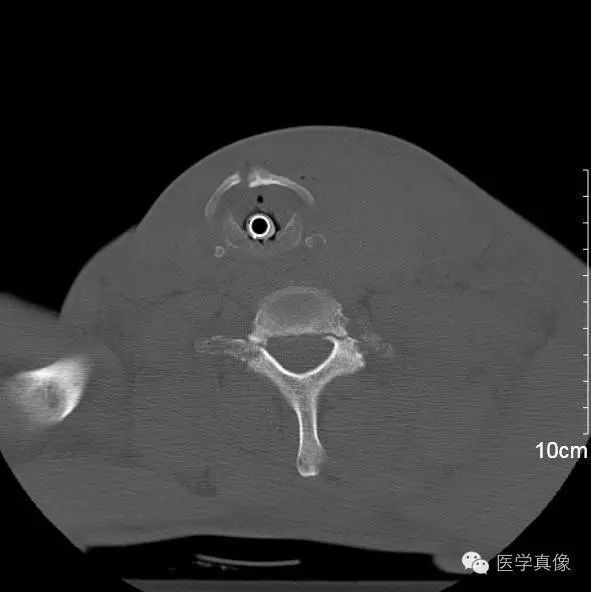

3、知识缺乏之错

发现一个病理征象,因知识匮乏未能做出正确解释。这类错误占比约3%,比如下图为颈椎骨折,但因不认识甲状软骨骨折而将其漏诊。